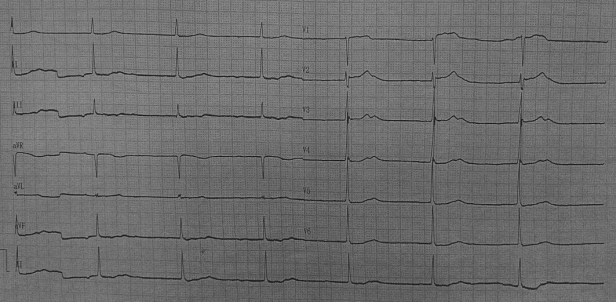

病例1

患者,58岁,女性,因“活动后气促伴心跳加速3月入院”,诊断为“风湿性二尖瓣狭窄瓣关闭不全(重度)、三尖瓣关闭不全(中度)、持续性心房颤动、心功能III级”,遂行二尖瓣机械瓣瓣膜置换术+三尖瓣成形术+心脏射频消融术+左心耳切除术,术后即刻房颤消失,恢复良好。

术前心电图